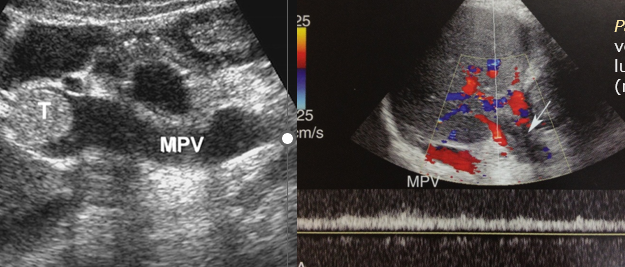

portal vein thrombosis (PVT)